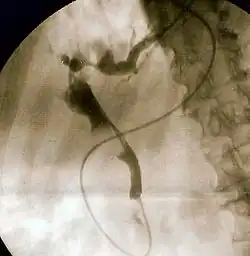

| Duodenoscopy image of pus extruding from the ampulla of Vater, indicative of cholangitis | |

The gold standard test for biliary obstruction is still endoscopic retrograde cholangiopancreatography (ERCP). This involves the use of endoscopy (passing a tube through the mouth into the esophagus, stomach and thence to the duodenum) to pass a small cannula into the bile duct. At that point, radiocontrast is injected to opacify the duct, and X-rays are taken to get a visual impression of the biliary system. On the endoscopic image of the ampulla, one can sometimes see a protuberant ampulla from an impacted gallstone in the common bile duct or the frank extrusion of pus from the common bile duct orifice. On the X-ray images (known as cholangiograms), gallstones are visible as non-opacified areas in the contour of the duct. For diagnostic purposes, ERCP has now generally been replaced by MRCP. ERCP is only used first-line in critically ill patients in whom delay for diagnostic tests is not acceptable; however, if the index of suspicion for cholangitis is high, an ERCP is typically done to achieve drainage of the obstructed common bile duct.[1]

Endoscopic retrograde cholangiopancreatography (ERCP) is the most common approach in unblocking the bile duct. This involves endoscopy (passing a fiberoptic tube through the stomach into the duodenum), identification of the ampulla of Vater and insertion of a small tube into the bile duct. A sphincterotomy (making a cut in the sphincter of Oddi) is typically done to ease the flow of bile from the duct and to allow insertion of instruments to extract gallstones that are obstructing the common bile duct; alternatively or additionally, the common bile duct orifice can be dilated with a balloon.[15] Stones may be removed either by direct suction or by using various instruments, including balloons and baskets to trawl the bile duct in order to pull stones into the duodenum. Obstructions that are caused by larger stones may require the use of an instrument known as a mechanical lithotriptor in order to crush the stone prior to removal.[16] Obstructing stones that are too large to be removed or broken mechanically by ERCP may be managed by extracorporeal shock wave lithotripsy. This technique uses acoustic shock waves administered outside the body to break down the stones.[17] An alternative technique to remove very large obstructing stones is electrohydraulic lithotripsy, where a small endoscope known as a cholangioscope is inserted by ERCP to directly visualize the stone. A probe uses electricity to generate shock waves that break down the obstructing stone.[18] Rarely, surgical exploration of the common bile duct (termed choledochotomy), which can be performed with laparoscopy, is required to remove the stone.[19]